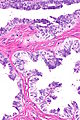

Adenomatous hyperplasia of the rete testis

Adenomatous hyperplasia of the rete testis. H&E stain. | |

| LM | epithelium with tubulopapillary or cribriform architecture separated by small amount of stroma |

Adenomatous hyperplasia of the rete testis (abbreviated AHRT), also rete testis adenomatous hyperplasia, is a rare benign lesion of the rete testis that may be confused with malignancy.[1][2]

- Epithelium with tubulopapillary or cribriform architecture separated by small amount of stroma.